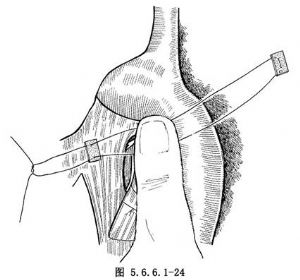

如肿瘤位置较高不能作弓下吻合,应作主动脉弓上吻合,需要将食管继续向上游离。在主动脉弓下缘常有1~2支直接来源于主动脉的食管固有动脉供应食管,要仔细分出,用丝线结扎后切断,不能贸然剪断,否则将造成危险的大出血(图5.6.6.1-21)。一旦固有动脉被损伤,切记不可用止血钳乱夹,术者可用右手示指尖按压出血处(图5.6.6.1-22)。然后用无损伤针及2/0号涤纶线携带一个1cm×1.5cm大的涤纶补片,由按压出血处的示指端右缘进针,由指端左缘出针,用缝线另一端的针由距离前一针0.6cm处的下方再缝一针(图5.6.6.1-23)。两根针再次穿过另一块补片(图5.6.6.1-24)。抽出按压出血处的手指,结扎涤纶线(图5.6.6.1-25)。每个缝线打结6次,如仍有小渗血可补缝数针。正确处理食管在主动脉弓下的固有动脉的方法为由主动脉弓下缘仔细解剖,找出血管后结扎,或切开主动脉弓上缘的纵隔胸膜,用手指由主动脉弓后方、食管前壁与主动脉弓之间轻轻向下外方向顶,即可将固有动脉由弓下显露。如固有动脉位置较深,可用手指尖端由主动脉下方,食管前壁与主动脉弓之间轻轻向上顶,即可将固有动脉由弓上显露(图5.6.6.1-26)。将固有动脉处理完后,即可将已在贲门处切断的食管由主动脉后方提至弓前方作吻合(图5.6.6.1-27)。